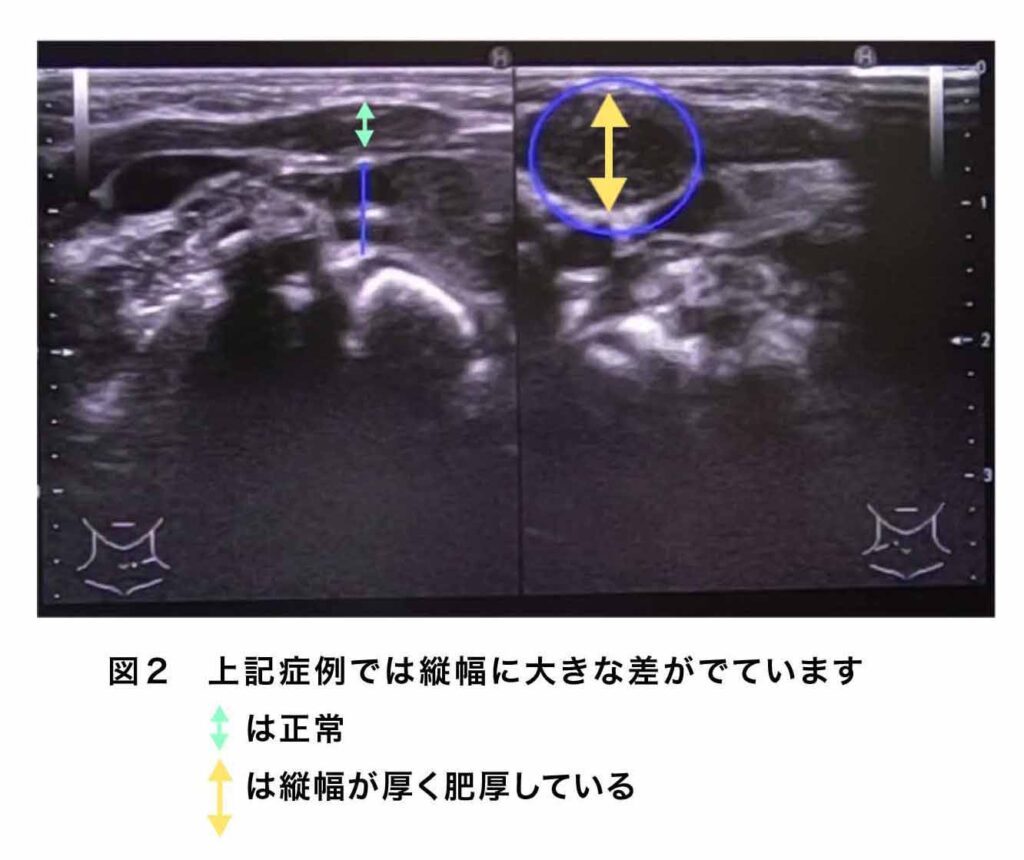

超音波検査では胸鎖乳突筋の中にしこりが確認され、胸鎖乳突筋に左右差が生じていることが確認されます。またその内部輝度(画像上の光り輝く度合)にも左右差が見られることもしばしばです。(図2)